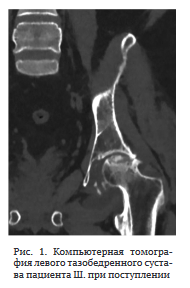

07.03.23 произведена операция в объеме резекции головки бедренной кости, установки артикулирующего спейсера из костного цемента с клиндамицином (4,5 г) (рис. 5). Выбор клиндомицина обусловлен близким к линкомицину механизмом действия и антимикробным спектром (в анамнестических данных пациента есть указания на положительный эффект применения линкомицина), а также высокой элюционной способностью препарата [25].

Послеоперационных осложнений не отмечено, больной приступил к ходьбе с дополнительной опорой на вторые сутки после операции. Выписан под наблюдение травматолога-ортопеда и инфекциониста.

Повторно госпитализирован через шесть месяцев. Местный статус: укорочения правой нижней конечности нет. Послеоперационный рубец — без признаков воспаления.

Функциональные показатели сустава по шкале HHS — 77, по шкале WOMAC — 24, выраженность болевого синдрома по шкале ВАШ — 2 балла. При пальпации обнаружена незначительная локальная болезненность в проекции правого тазобедренного сустава (2 балла по шкале ВАШ).

Рентгенограмма представлена на рис. 6.

Выполнена пункция периимплантного пространства из трех точек. При микробиологическом исследовании операционного материала роста микрофлоры не выявлено.